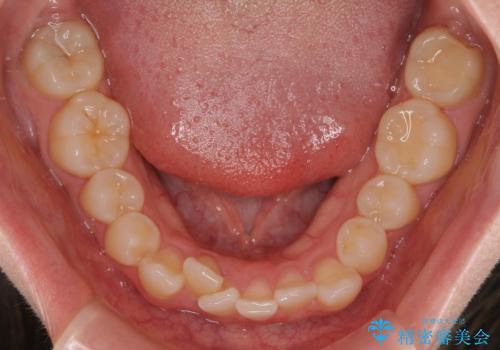

- 八重歯が気になるとのことで来院された患者様です。

上顎前歯部はデコボコが強く、歯を並べるためのスペースが不足しているため、左右の第一小臼歯を抜歯することとしました。